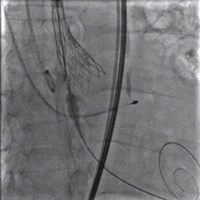

手术影像

主动脉根部造影

20mm球囊预扩后瓣膜开始定位

工作位造影:左右窦侧瓣架偏深

回收后重新调整释放

工作位造影:位置理想

瓣膜逐个缓慢脱钩

23mm球囊后扩改善形态

最终造影:位置理想,形态良好,无漏